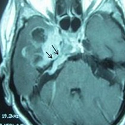

Une métastase cérébrale révélée par une otomastoïdite chronique

Brahim Eljebbouri, Ali Akhaddar

PAMJ. 2014; 18: 19. Published 06 May 2014